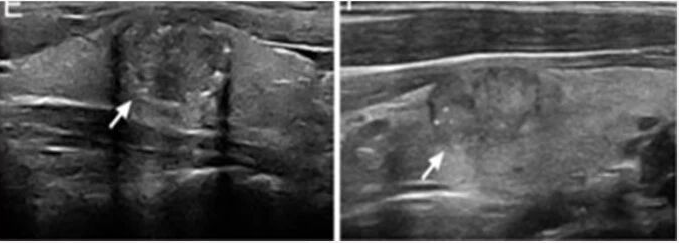

二、超声怎么看结节?——六大“悬疑线索”

超声医生像侦探一样,通过观察结节的以下特征来评估风险:

1.形态与边界:良性“标签”:形态规则(圆形/椭圆形)、边界清晰,像一颗光滑的珍珠。恶性“疑点”:形态不规则、边界模糊或呈“蟹足样”浸润。

2.内部回声:良性“标签”:无回声(纯囊性,像水泡)或高回声,通常安全。恶性“疑点”:低回声或极低回声,实体成分多。

3.纵横比(结节前后径与左右径的比值):这是一个重要指标。良性“标签”:结节“躺平”生长,纵横比<1。恶性“疑点”:结节“直立”生长,纵横比≥1(像立着的鸡蛋)。

4.钙化:微钙化(像沙粒一样细小的强光点) 是恶性风险较高的一个特征。

5.血流信号:内部血流紊乱、丰富,可能提示生长活跃。

6.淋巴结:检查颈部淋巴结是否有异常(如囊性变、微钙化、高回声团、变圆),这是判断有无转移的关键。